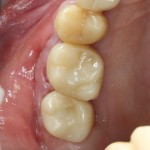

Через пару недель область, где мы провели уже две операции, выглядит примерно так:

или, если снять формирователи:

Можно передавать пациента ортопеду для временного протезирования. Что он и делает:

Важным условием гарантийных обязательств в нашей клинике являются профилактические осмотры, которые проводятся один или два раза в год (см. Гарантии и Долгосрочное наблюдение). Через полтора года после протезирования, при очередном осмотре мы сделали фотографии и снимок: